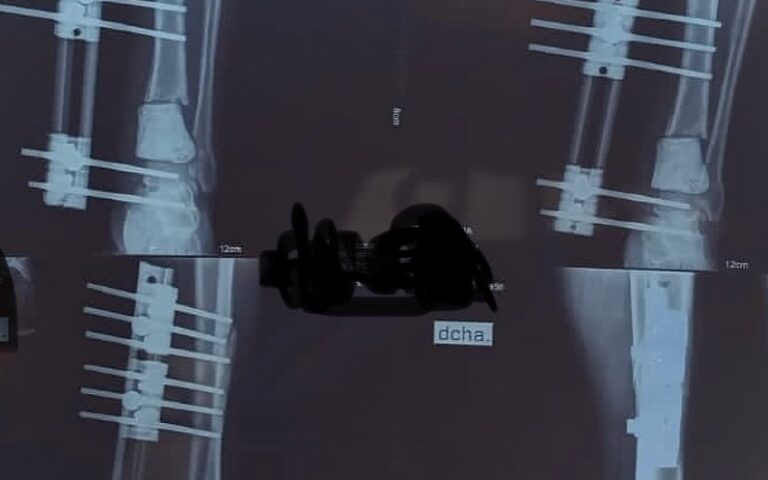

El Dr. Escobar es un destacado cirujano ortopédico especializado en tobillo y pie, con más de 15 años de experiencia en el ámbito de la traumatología. Su enfoque está orientado a brindar atención de calidad, respaldado por una sólida formación académica y práctica. A lo largo de su carrera, ha trabajado tanto en instituciones públicas como privadas, combinando su pasión por la cirugía con un compromiso continuo hacia la actualización médica.

Durante su trayectoria, ha participado en diversas rotaciones, pasantías y certificaciones, lo que le ha permitido consolidarse como un referente en su especialidad. Actualmente, forma parte del staff de ortopedia y traumatología en el Hospital Zonal Dr. Natalio Burd y en el Centro Traumatólogos Neuquén, donde continúa aplicando sus conocimientos y habilidades para mejorar la calidad de vida de sus pacientes.